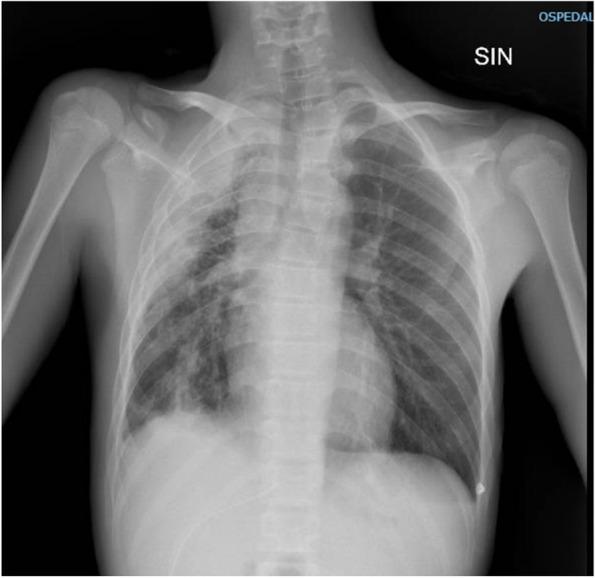

We report the case of a 15-year-old previously healthy boy diagnosed with both pulmonary empyema and subphrenic chest wall abscess caused by Aa. He was admitted to our Pediatric Emergency department for evaluation of a right mass associated with marked asthenia and dry cough. After radiological findings etiological diagnosis was made by culture of fluid drainage of pleural empyema. He started empirical antibiotic therapy with intravenous piperacillin/tazobactam, whose sensibility was confirmed by the antibiogram, then, for occurrance of hepatopathy it was switched to ciprofloxacin: the patient almost completely recovered after 6-month therapy.

我们报告了一例 15 岁既往健康的男孩,被诊断为 Aa 引起的肺脓胸和膈下胸壁脓肿。他因右肺肿块伴明显乏力和干咳而被收入我院儿科急诊。在影像学检查后,通过胸腔积液引流的培养进行了病因诊断。他开始接受经验性抗生素治疗,静脉注射哌拉西林/他唑巴坦,药敏试验证实了抗生素的敏感性,然后因出现肝损伤而改用环丙沙星:患者在 6 个月的治疗后几乎完全康复。